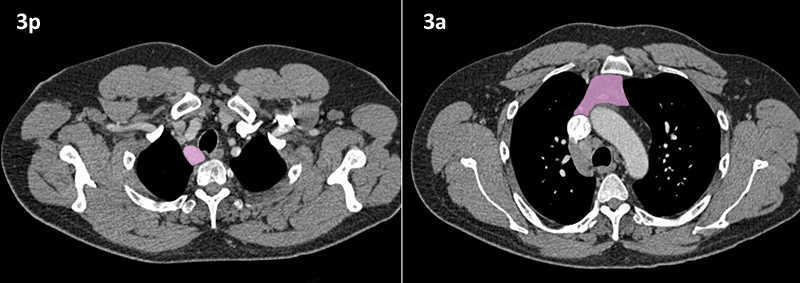

Nodal zones and stations according to the International Association for the Study of Lung Cancer (IASLC) node map.

Table (above): Nodal zones and stations according to the International Association for the Study of Lung Cancer (IASLC) node map. (Source: 1,2) *Depends on the side of the tumour.